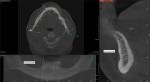

A large field of view CBCT scan was acquired to assess the surgical and prosthetic needs of the candidate (Figure 1). In addition, the patient's phonetics, esthetics, function, vertical dimension of occlusion, smile, and transition lines, among other clinical characteristics, were evaluated and documented (Figure 2). Upon completion of the examination, it was determined that rehabilitation with a full-arch fixed removable denture with narrow platform implants was a viable and acceptable option.3